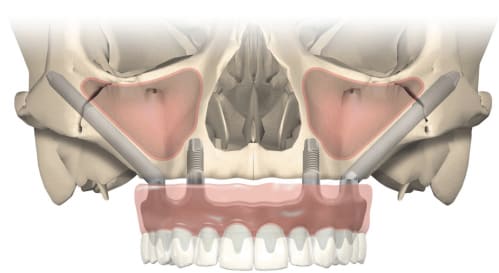

Jochbein-Implantate

Dies ist der am wenigsten häufig verwendete Implantattyp. Bei zygomatischen Implantaten wird der Jochbeinknochen zur Platzierung und Verankerung des Zahnersatzes für den Oberkiefer genutzt. Auch sie werden in der Regel in Betracht gezogen, wenn die Knochenstruktur für enossale Implantate nicht geeignet ist.